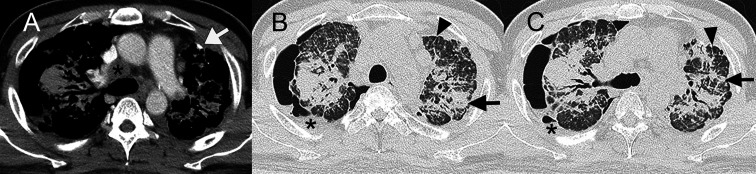

本报告重点关注在厨房台面生产中使用含有高结晶二氧化硅的人造石所带来的职业健康风险。报告一名43岁男子因从事切割和抛光石英石原料的工作而患上严重矽肺。对患者的医疗记录和职业史进行了回顾性分析。根据临床表现、肺功能检查、放射学表现和组织学报告,诊断为严重矽肺、中度限制性肺病和双侧肺气肿。患者接受了肺移植,术后肺功能有所改善。该研究强调了与人造石相关的重大健康风险,并强调了员工和工人意识和保护措施的重要性。临床医生在诊断有职业接触过含有高结晶二氧化硅的人造结石史的患者的呼吸道症状时应谨慎。

This report focuses on the occupational health risks associated with the use of artificial stones containing high levels of crystalline silica in the production of kitchen countertops. It presents the case of a 43-yr-old man who developed severe silicosis due to his occupation involving cutting and polishing quartz stone raw materials. A retrospective analysis of the patient's medical records and occupational history was conducted. The diagnosis of severe silicosis, moderate restrictive lung disease, and bilateral pneumothorax was based on clinical manifestations, pulmonary function test, radiological findings, and histological reports. The patient underwent lung transplantation, and his pulmonary function improved post-surgery. The study highlights the significant health risks associated with procedures involving artificial stones and emphasizes the importance of awareness and protective measures for employees and workers. Clinicians should be cautious when diagnosing respiratory symptoms in patients with a history of occupational exposure to artificial stones containing high levels of crystalline silica.